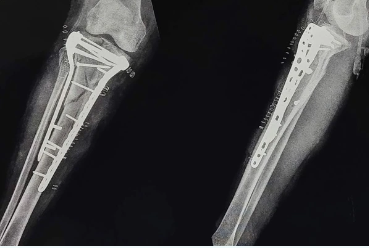

Best orthopedic center . Multi ligament knee injury is complex injury. It can be treated effectively by minimally invasive arthroscopic surgeries. For more information visit our site Book appointment with expert arthroscopy surgeon .